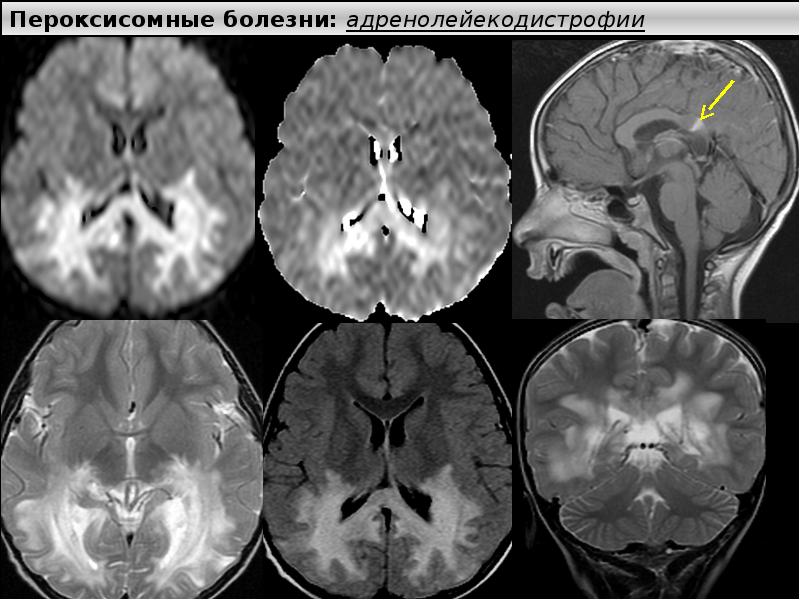

Хроническая ишемия головного мозга и лейкоареоз: симптомы и лечение